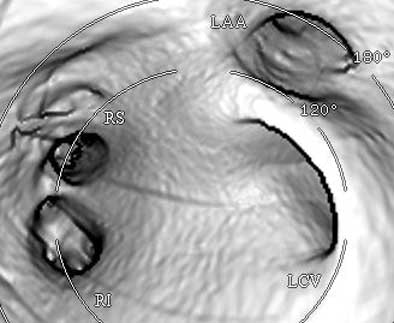

![]() |

| Endocardial (above) and epicardial (below) views from a patient with a long-trunk left common vein (LCV) and separate RS and RI veins. There are a total of three pulmonary veins. (LAA = orifice of the left atrial appendage.) Images courtesy of Dr. Joan Lacomis. |

Pulmonary vein anatomy varies widely, and right-side anatomy tends to be more complex than the left side, she said. At her institution, a third of patients have been found to have accessory veins, she said, usually on the right side (87%). Conjoined veins are less common (10%) and usually occurred on the left side (88%). About 70% of patients in the past five years have been reported to have the classic fourth pulmonary vein, and some form of variant PV anatomy is present in about 30%-40% of patients. Long-trunk common veins are easy to diagnose, short-trunk common veins more difficult, she said.

Endocardial volume-rendered views of the right and left pulmonary inflow vestibules show the imaging volume from the intra-atrial perspective. They are useful for assessing global size, the shape and volume of the left atrium, the number of veins, accessory veins, and conjoined veins, and for examining the ostial branches and their intravenous saddles, the region of the atrial wall interposed between separate ipsilateral pulmonary veins.